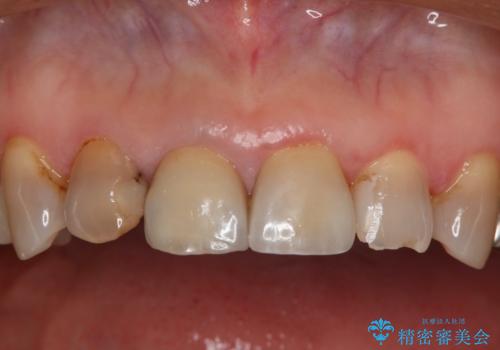

- 右上2番の審美性改善を主訴に来院された患者様です。

切削量と前歯ということからオールセラミッククラウンでの治療を選択しました。

前歯では審美性の高いオールセラミッククラウンでの治療を選択される患者様が多いです。